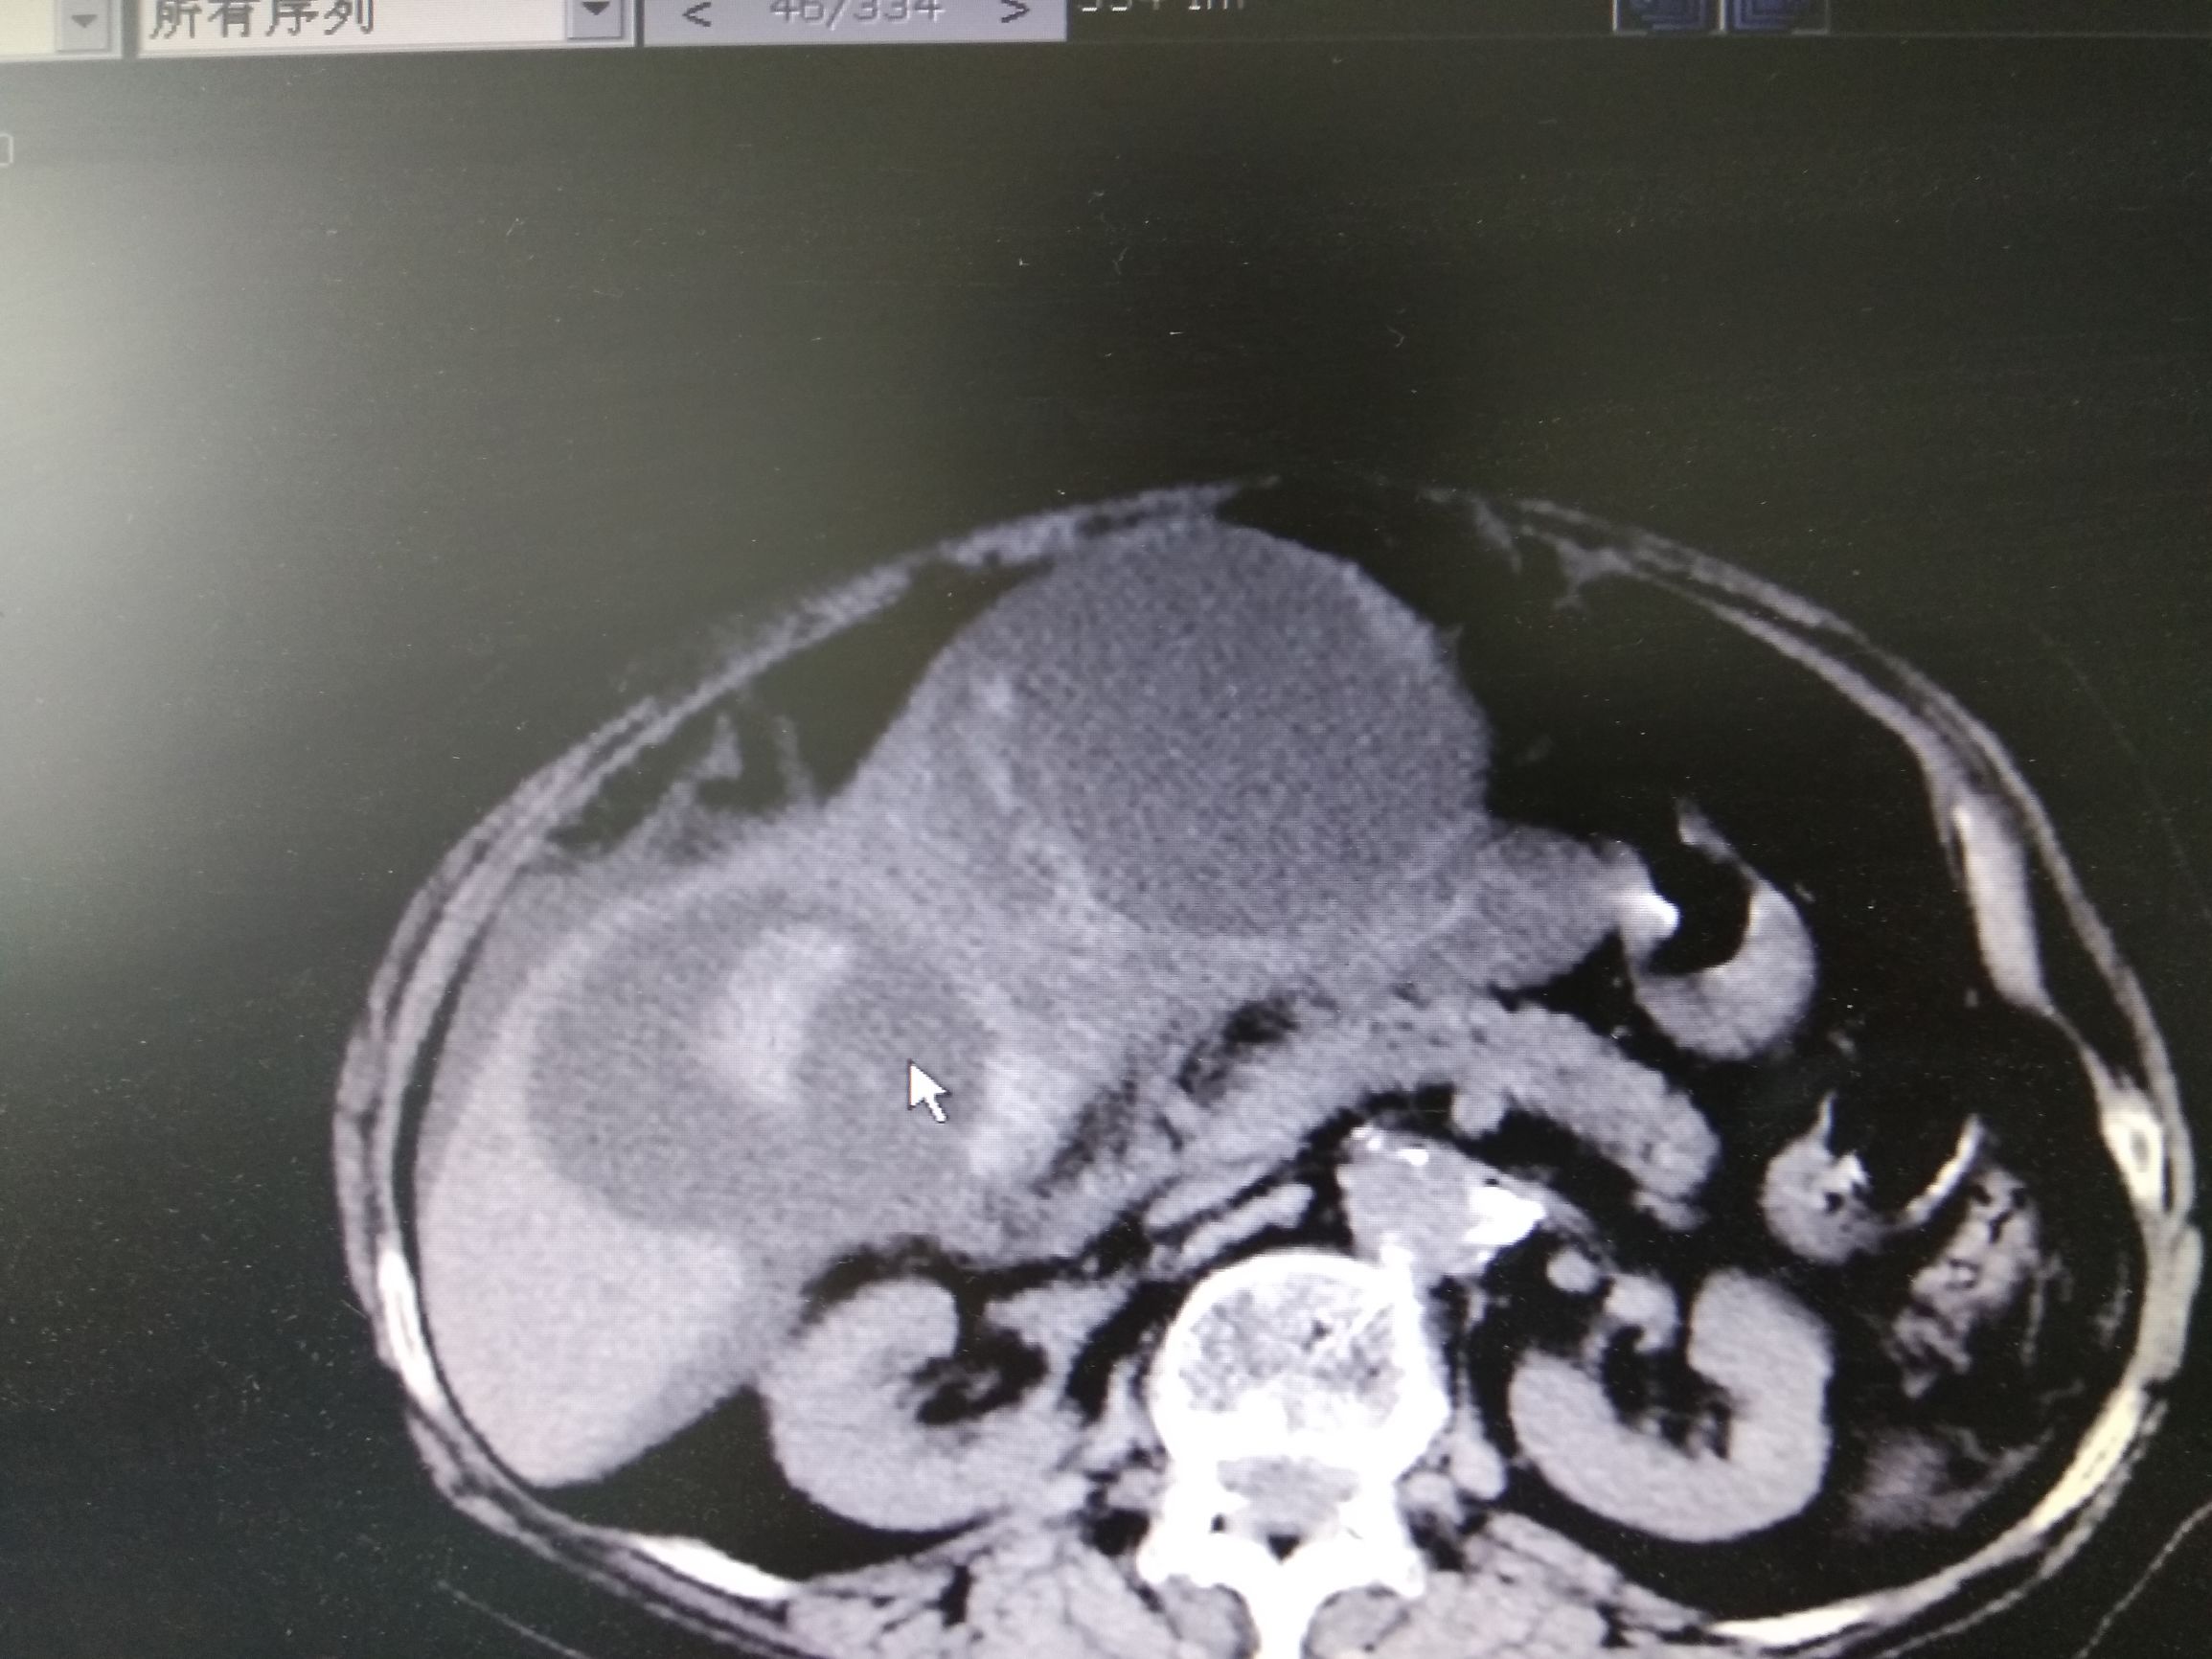

可是过了不到一个月李奶奶再次出现了腹胀,并且伴有发热,李奶奶再次来到了医院,医生复查CT,CT结果囊肿又变大了,而且囊肿里面有高密度,医生解释那有可能是出血,于是李奶奶再次做了穿刺抽液,抽出来的是血性混浊的液体,但是过了几天再次复查积液又多了,而且发热症状不缓解,这时候医生开始怀疑病人的疾病可能不是简单的肝囊肿,做了肝脏强化CT检查,并且检查了肿瘤标记物,CA199,CEA升高,在查阅很多文献,以及请相关专家会诊以后考虑李奶奶这个病就是肝脏囊腺癌,是一种比较少见的肝脏癌症。